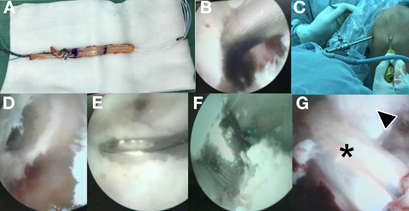

Consulta en el servicio de ortopedia infantil presentando al examen físico inestabilidad anterior dada por el test de Lachman positivo. Concomitantemente presentaba dolor a nivel de la interlínea interna, siendo positivas las pruebas de McMurray y Apley en relación al menisco interno. Se solicitaron radiografías anteroposterior (AP) y perfil (P) de la rodilla lesionada en busca de otras lesiones, siendo estas normales. Se solicitó una resonancia nuclear magnética (RNM) de la rodilla derecha, evidenciándose la rotura de LCA y una lesión longitudinal del cuerno posterior del menisco interno (Figura 1). Se coordina para cirugía artroscópica con el planteo de realizar una reconstrucción transfisaria del LCA y una reparación inside - out del menisco interno, al año de producida la lesión. Se realizaron en este momento los scores de Tegner & Lysholm, además del IKDC previos a la cirugía (Tabla 1 y 2).

Figura 1. RNM de rodilla derecha de paciente adolescente de 14años. A. Corte sagital en T2 que muestra (flecha negra con borde blanco) la ausencia de LCA. B y C. Corte sagital y axial en T2 que a su vez hace notar una lesión longitudinal periférica del cuerno posterior a nivel de la zona roja - roja del menisco interno (flecha blanca con borde negro).

Figura 2. Imágenes del intraoperatorio de la reparación inside out del menisco interno. A y B. Vista artroscópica que evidencia la lesión meniscal interna y rotura del LCA respectivamente. C. Abordaje posterointerno desde el tubérculo del aductor hacia platillo interno. D. Colocación del retractor posterior con rodilla a 90 grados evitando lesiones neurovasculares. E y F. Primer punto de sutura. G. Ayudante recuperando la aguja. H e I. Segundo punto de sutura. J. Se comprueba estabilidad posterior del menisco.

Figura 3. Imágenes del intraoperatorio de la plastia de LCA. A.Injerto de partes blandas (pata de ganso) utilizado. B y C. Colocación de la aguja de Kirschner (kw) guía para el túnel femoral. D. Imagen del túnel femoral. E. Posición de la guía para el túnel tibial. F. Mechado del túnel tibial. G. Resultado final con el injerto fijo y tenso (asterisco negro), y su relación con el ligamento cruzado posterior (flecha negra con borde blanco)